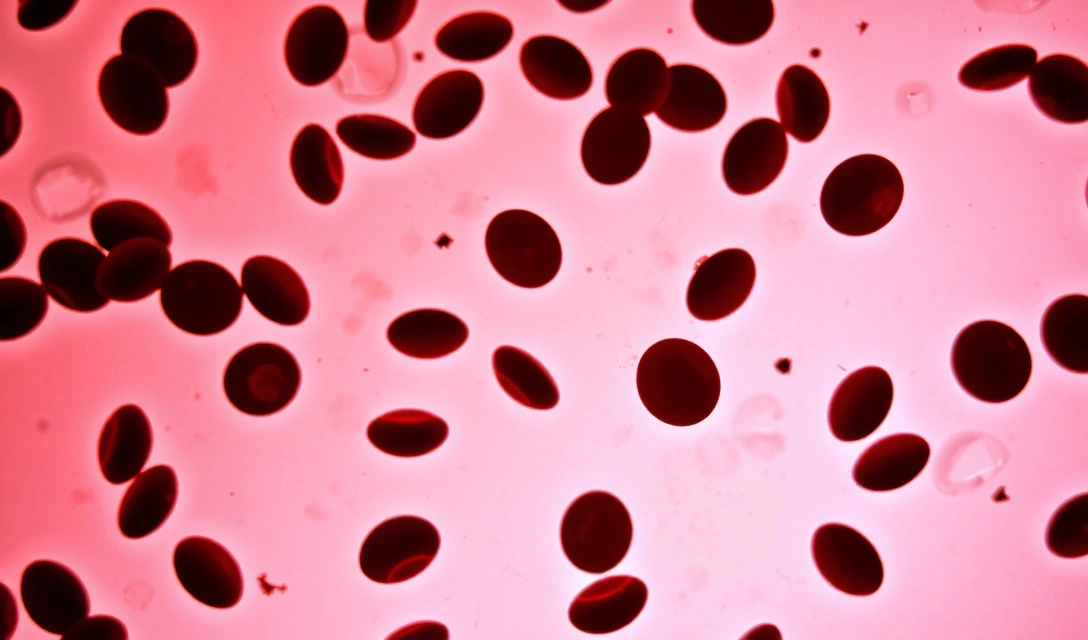

Υποστήριξη της πήξης του αίματος

Η πιο γνωστή λειτουργία της βιταμίνης K είναι ο κεντρικός της ρόλος στη διαδικασία της πήξης του αίματος. Είναι απαραίτητη για τη σύνθεση τεσσάρων από τους 13 παράγοντες πήξης που παράγονται στο ήπαρ. Χωρίς επαρκή βιταμίνη K, το αίμα δεν θα μπορούσε να πήξει σωστά, οδηγώντας σε αυξημένο κίνδυνο αιμορραγίας. Αυτός ο μηχανισμός είναι κρίσιμος για την επούλωση πληγών και την αποτροπή υπερβολικής απώλειας αίματος.

- Διαταραχές πήξης αίματος: Το πιο χαρακτηριστικό σύμπτωμα είναι η αυξημένη τάση για αιμορραγία. Αυτό μπορεί να εκδηλωθεί ως εύκολη εκχύμωση (μελανιές), αιμορραγίες από τη μύτη, τα ούλα, ή παρατεταμένη αιμορραγία από μικρές πληγές. Σε σοβαρές περιπτώσεις, μπορεί να οδηγήσει σε εσωτερικές αιμορραγίες.

- Εκχύμωση: Η εμφάνιση μωλώπων με ελάχιστο ή καθόλου τραυματισμό είναι συχνό σημάδι έλλειψης βιταμίνης K.

- Αίμα στα ούρα ή στα κόπρανα: Αυτό μπορεί να υποδηλώνει εσωτερική αιμορραγία στο ουροποιητικό ή πεπτικό σύστημα.